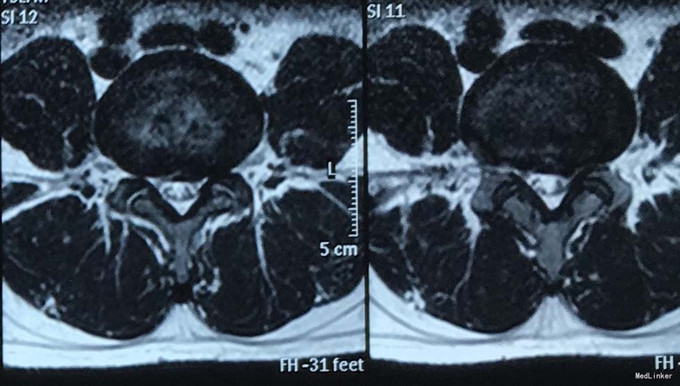

查体:脊柱生理弯曲存在,腰椎活动受限,L4/L5,L5/S1棘突压痛叩痛,叩击痛。左侧直腿抬高试验(+),约35°,加强试验(+),约30°。左下肢外侧皮肤感觉稍减退,右侧正常。双侧髂腰肌、股四头肌肌力Ⅴ级、左侧胫前肌、踇背伸肌肌力Ⅳ级,腹壁反射、肛门反射正常,两侧膝正常,双侧踝反射对称减弱。双侧Babinski征(-),双侧皮温及色泽正常,双侧足背动脉搏动良好。 辅助检查:腰椎磁共振检查显示:腰4/5椎间盘向左后方突出,压迫左侧神经根。骶管骶4水平发现一大小约2*3*3大小的囊肿。

诊断:1.腰4/5椎间盘突出症;2.骶管囊肿; 治疗:给予行左侧腰4/5椎板间开窗髓核摘除术。术后左腰臀部疼痛缓解明显,瞩其定期复查腰椎核磁共振。